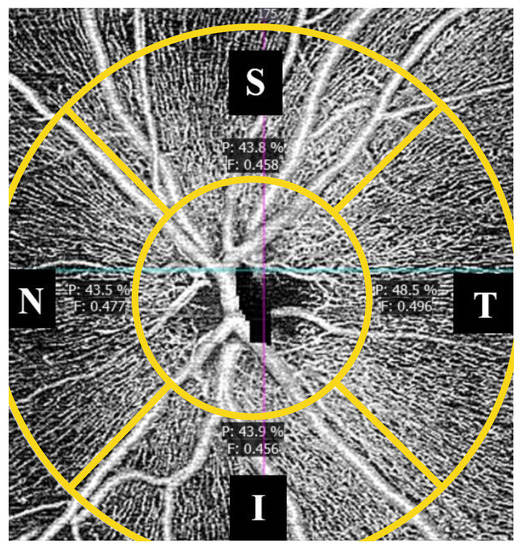

3. Results